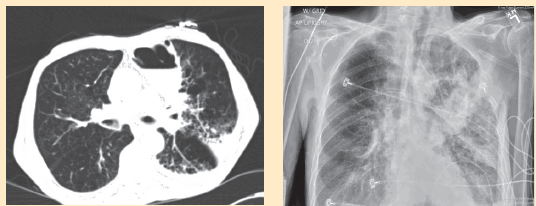

His initial vital signs were significant for a heart rate of 105 beats per minute, blood pressure of 104/76 mm Hg, and an oxygen saturation level of 93% on room air. Significant physical examination findings included cachexia and a sacral ulcer. His lungs showed vesicular breath sounds with crackles in the left upper lobe. Laboratory values indicated no leukocytosis, and his electrolyte panel, blood urea nitrogen level, and creatinine level were all within normal limits. A chest radiograph (Figure 1) and computed tomography (CT) scan of his chest (Figure 2) showed significant findings.

Figure 1. Chest radiograph shows a focal area of consolidation in the left lung.

Figure 2. Computed tomography scan of the patient’s chest shows an air-fluid level with a surrounding infiltrate.